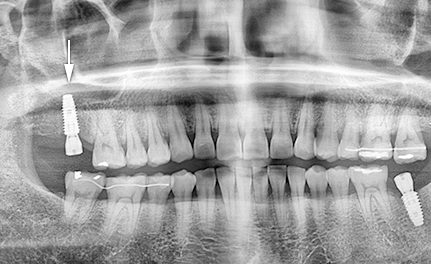

임플란트는 흔히 수복물이라고 고민하고 단순히 치아와 크라운으로만 생각하기 쉽지만, 그 이상으로 유지장치의 뿌리에 인공치아(유지장치)를 이식하여 임플란트를 제작하는 경우도 있습니다. 총 3가지 유형이 있습니다. 결합하여 임플란트를 형성합니다. 그러므로 가격대가 어떠한 브랜드인지 분명하게 정의하기 어렵고, 어느 수준의 가격을 지출하는지 역시 어떠한 크라운을 활용할 것인지 등 가격대를 선택하는 필요한 요소입니다.

표면처리 방법은 다양하며, 비용 등 여러가지 시점에서 선택하실 수 있습니다. 첫 번째는 표면처리가 필요 없어 인체에 안정된 RBM, 산처리를 통하여 골융합력을 올리는 SLA이다. Reality MegaGen 임플란트는 SLA보다 소비자 친화적이고 더 강한 것으로 간주되는 Blue Diamond로 저명한 순수 티타늄 유형으로 유명합니다. 그리고 강도와 크라운과의 호환성이 향상된 차세대 임플란트로 애니원 NI(AnyOne NI)가 출시되었습니다.

최근 몇 년간 가장 대중성 있는 디지털 임플란트 중 하나입니다. 모든 테스트는 디지털 방식으로 사전 시뮬레이션되기 때문에 최소한의 절개로 수행할 수 있다는 큰 좋은 점이 있습니다. 안전하고 과학적으로 임플란트 수술을 하고 싶다면 이 브랜드를 선택하세요. 최소절개로 여러가지 부작용과 아픔의 가능성을 줄여주기 때문입니다.